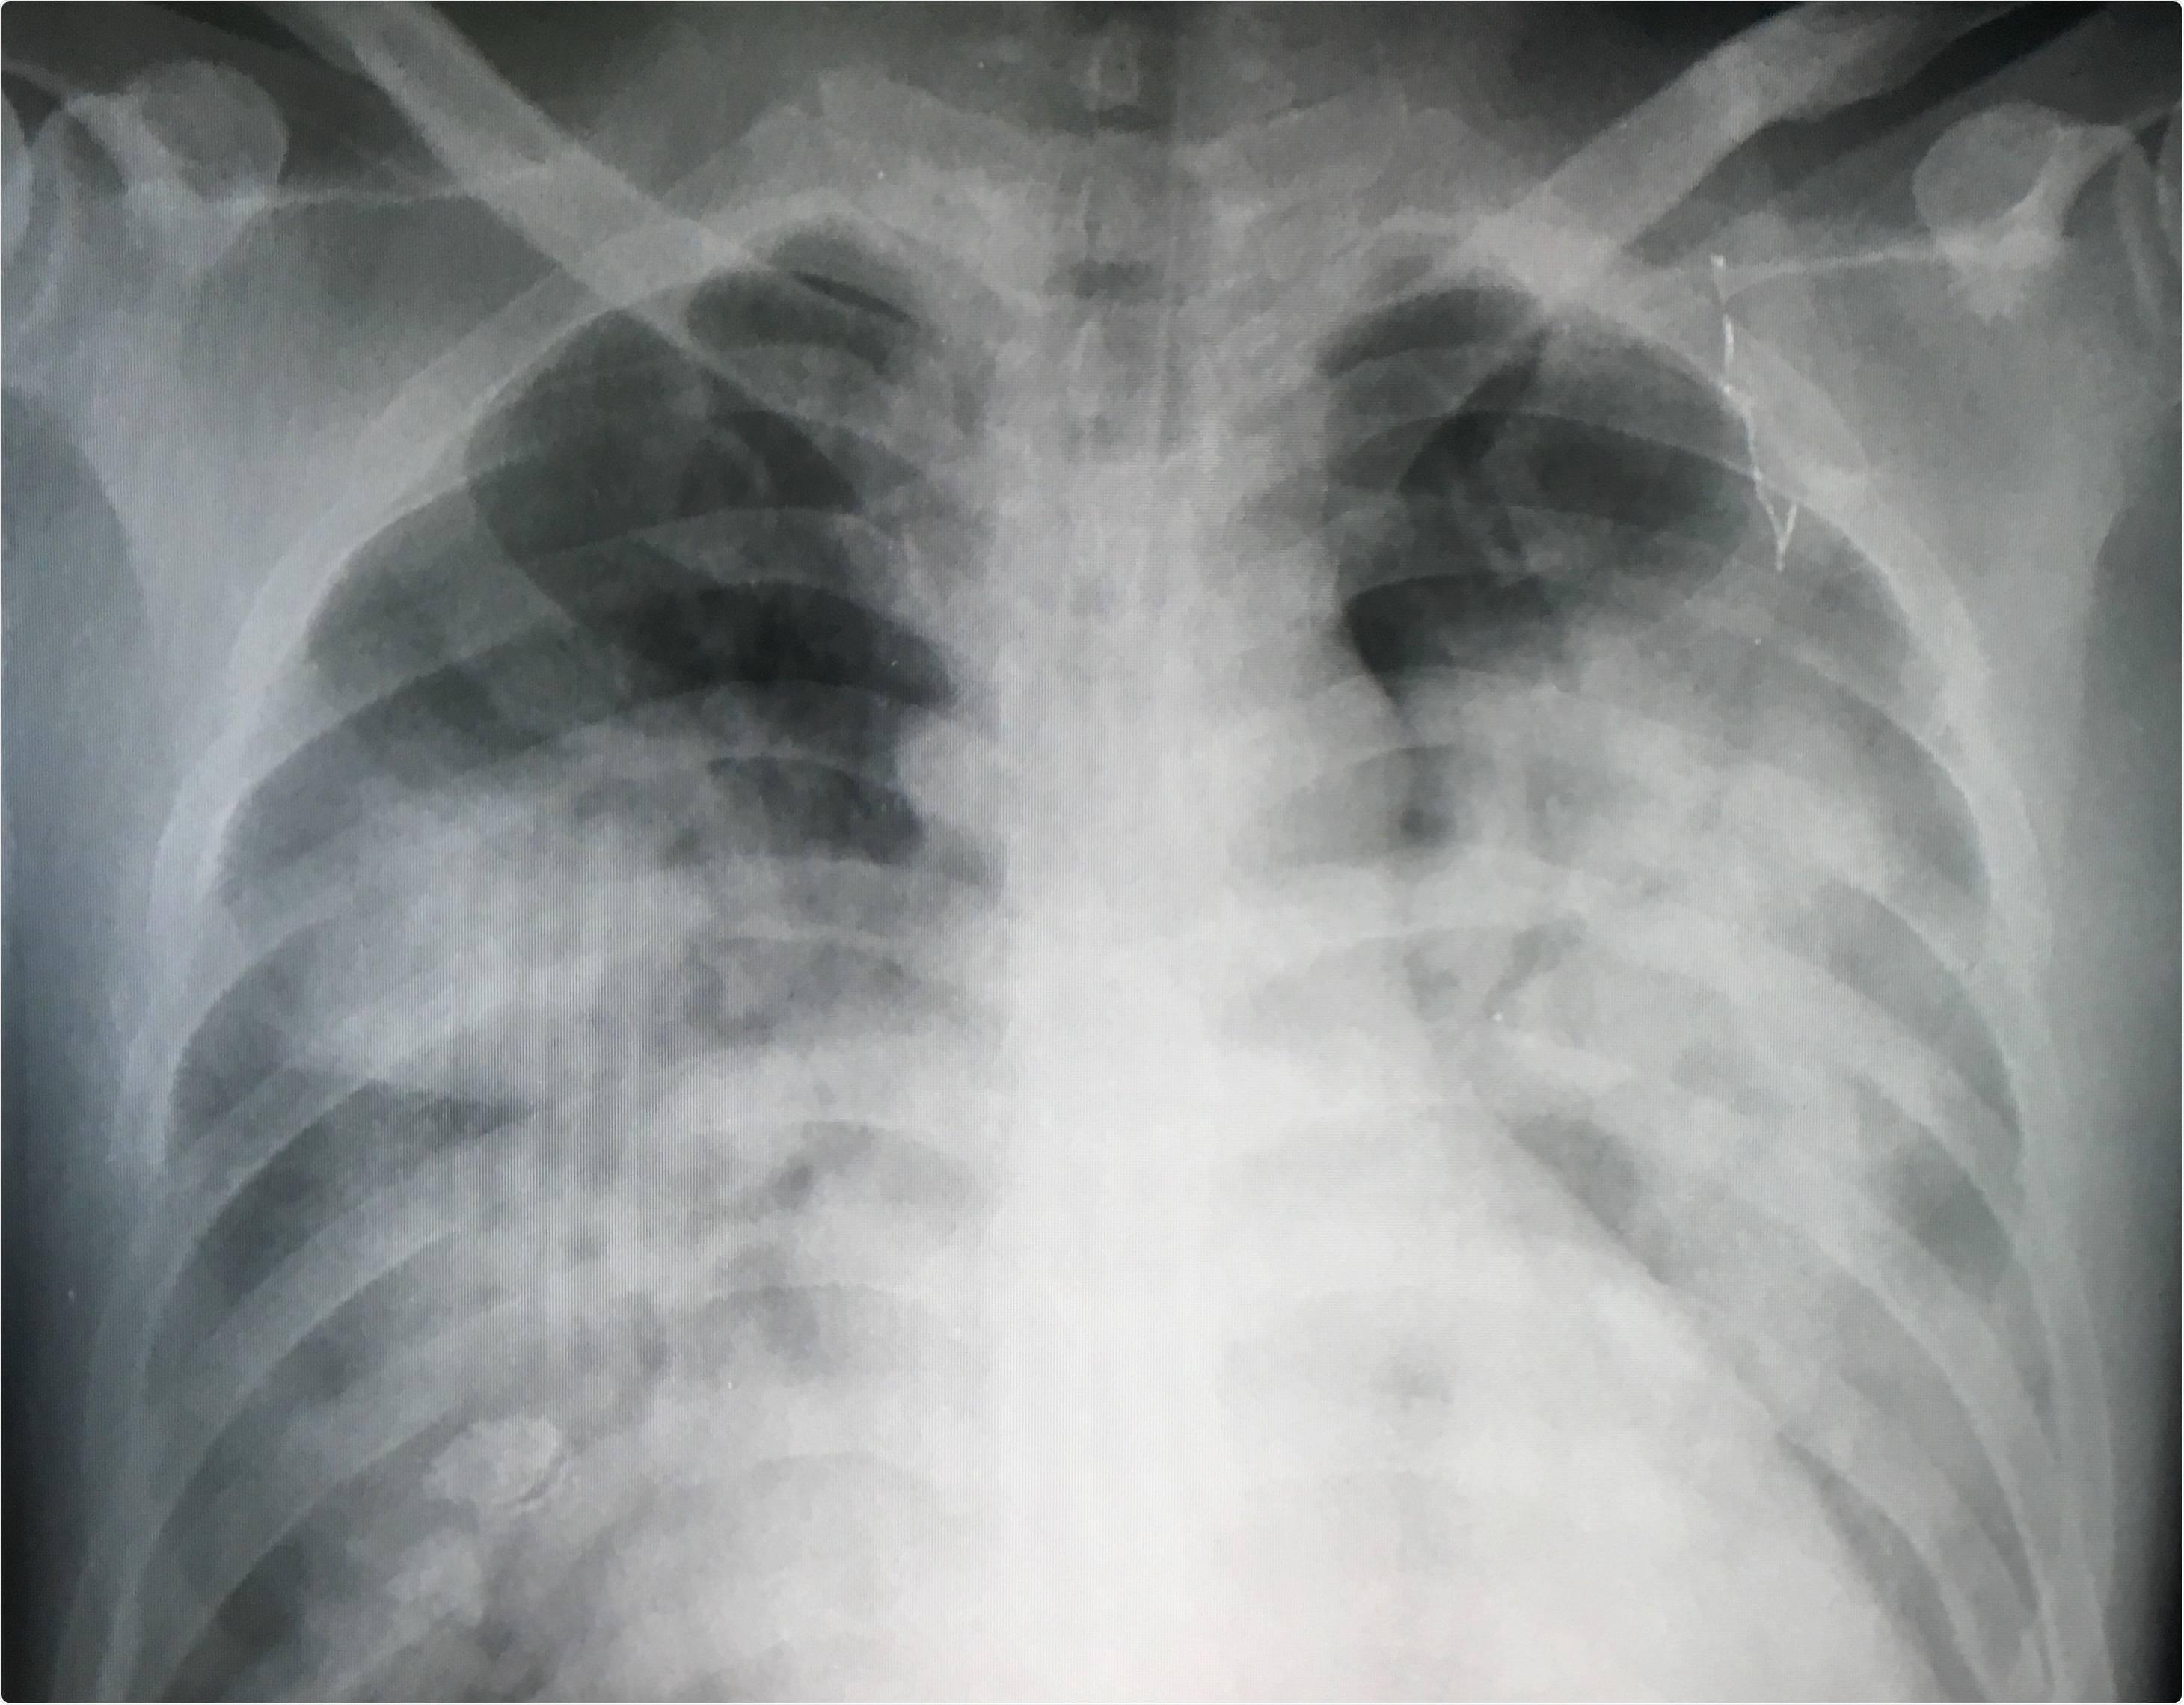

Oxygenation on Day 5 of treatment (day 6 following baseline) in the prostacyclin-treated group compared the control (NaCl)-treated group among A) all patients included in the trial and B) all COVID-19+ patients included in the trial.